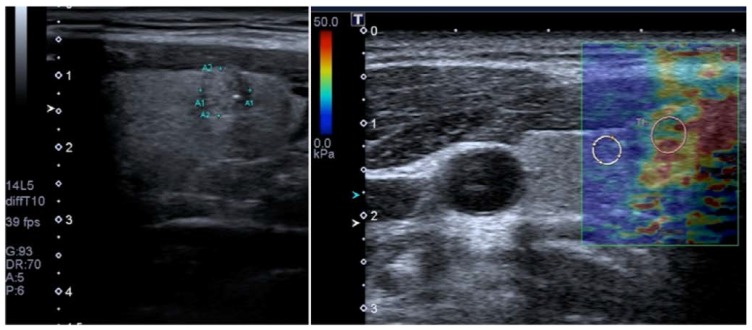

در SWI، یک اندازه گیری کمی از سرعت موج برشی (m/sec) یا مدول یانگ (kPa) در یک ضایعه یا به عنوان یک مقدار واحد در یک ناحیه کوچک ثابت مورد علاقه (ROI) یا برای هر پیکسل در یک میدان به دست می آید. کادر نمای (FOV) به صورت نقشه رنگی 19، 67 نمایش داده میشود. معمولاً از مقیاس رنگی از 0 (آبی تیره = نرم) تا 180 کیلو پاسکال (قرمز = سخت) در سینه USE 73 استفاده میشود (شکل 7).

نمایش کنار هم از تصویر آناتومیک B-mode ایالات متحده (سمت چپ) و نقشه رنگی روکش شده از اندازه گیری امواج برشی همزمان (سمت راست) یک ضایعه پستان که با 2D-SWE در SuperSonic Imagine (SSI) AixplorerTM به دست آمده است. در این سیستم رنگ قرمز نشان دهنده بافت سفت و رنگ آبی نشان دهنده بافت نرم است. ضایعه هیپواکوئیک مشکوک (در داخل مستطیل در تصویر حالت B نشان داده شده است) دارای حاشیه نامنظم، حاشیه های زاویه ای، کمی پهن تر از ارتفاع است و سایه های آکوستیک خلفی را نشان می دهد. الاستوگرام اتیولوژی بدخیم را به دلیل افزایش سفتی (قرمز/زرد/سبز) پیشنهاد کرد و آدنوکارسینوم مجرای در بیوپسی بعدی تایید شد. تصویر توسط دکتر اسمار سایتو.